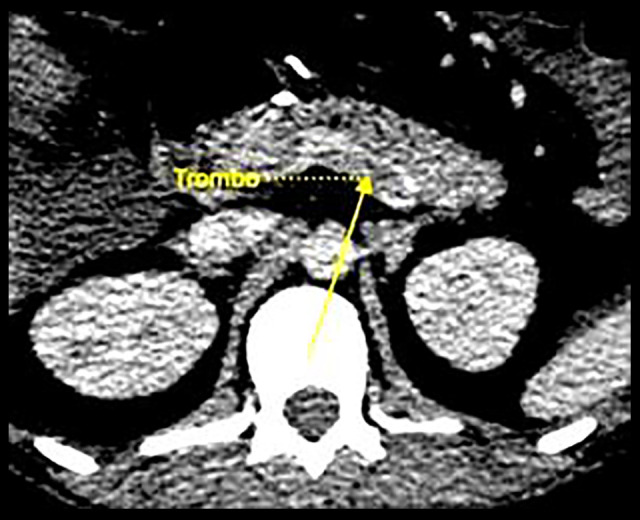

背景:自1980年以来,肥胖症的患病率增加了一倍多。因此,减肥手术率显著上升,增加了解决其并发症的需要。肠系膜静脉血栓形成是一种罕见但可能危及生命的并发症,占所有肠系膜缺血性事件的5%至15%。本病例强调了将肠系膜静脉血栓形成作为减肥手术的潜在并发症的重要性,特别是在高危患者中。病例报告一名28岁的II级肥胖女性接受了选择性腹腔镜袖式胃切除术。术后第7天,患者出现腹泻和呕吐(周末10次以上),黏膜干燥,模糊腹痛放射至腰部,口服不耐受。48小时后,没有任何改善,2024年1月7日,腹部和骨盆增强计算机断层扫描显示门静脉、肠系膜上静脉和脾静脉血管内缺损,提示血栓形成。结论:减肥手术后肠门静脉血栓形成的病因可能是多因素的。虽然静脉血栓栓塞与肥胖之间的关系已经确立,但尽管文献中已有预防措施,但关于出院后药物治疗的最佳持续时间仍存在争议。约95%的外科医生会在术后至少10至14天内使用抗凝剂,而50%的医生会将预防延长至30天,具体时间取决于个人的危险因素。虽然胃套管手术为肥胖患者提供了实质性的好处,但门脉肠系膜血栓形成的发病率不断上升,强调了积极预防和早期发现策略的重要性。

BACKGROUND The prevalence of obesity has more than doubled since 1980. Consequently, bariatric surgery rates have risen significantly, increasing the need to address its complications. Portomesenteric venous thrombosis is a rare but potentially life-threatening complication, accounting for 5% to 15% of all mesenteric ischemic events. This case highlights the importance of considering portomesenteric vein thrombosis as a potential complication in bariatric surgery, especially in patients at high risk. CASE REPORT A 28-year-old woman with grade II obesity underwent elective laparoscopic sleeve gastrectomy. On postoperative day 7, she presented with diarrhea and vomiting (over 10 episodes in a weekend), dry mucosa, vague abdominal pain radiating to the lumbar region, and intolerance to oral intake. After 48 h with no improvement, a contrast-enhanced abdominal and pelvic computed tomography scan (January 7, 2024) revealed intravascular defects in the portal vein, superior mesenteric vein, and splenic vein, suggesting thrombosis. CONCLUSIONS The etiology of portomesenteric vein thrombosis following bariatric surgery is likely multifactorial. While the relationship between venous thromboembolism and obesity is well established, debates persist regarding the optimal duration of medical therapy after discharge, despite the existing preventive measures in the literature. Some 95% of surgeons administer anticoagulants for at least 10 to 14 days postoperatively, while 50% extend prophylaxis for up to 30 days, depending on individual risk factors. While gastric sleeve surgery offers substantial benefits for patients with obesity, the rising incidence of portal mesenteric thrombosis underscores the importance of proactive prevention and early detection strategies.